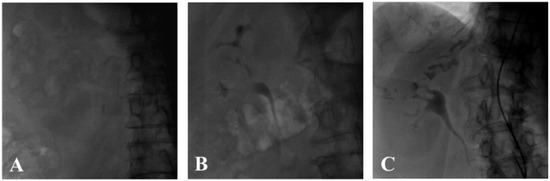

2.3. Renal Contrast Accumulation Analysis

3.2. Contrast Accumulation Score